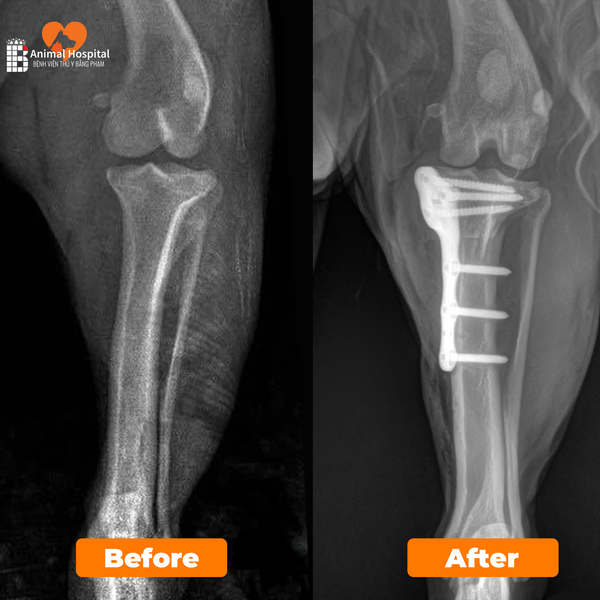

Dịch Vụ Phẫu Thuật Chỉnh Hình Xương Khớp

Thực hiện điều trị gãy xương, trật khớp và dị tật vận động bằng các kỹ thuật cố định tiên tiến như nẹp vít titan, giúp phục hồi chức năng vận động an toàn và bền vững cho thú cưng.